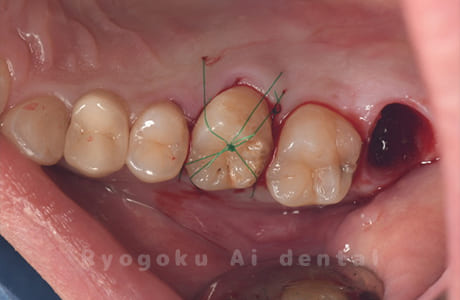

Case26

歯軋りが原因で奥歯を割ってしまった患者様です。下の親知らずを移植し、その際にサイナスリフトを行いました。問題なく経過し、患者様も大変満足されていました。